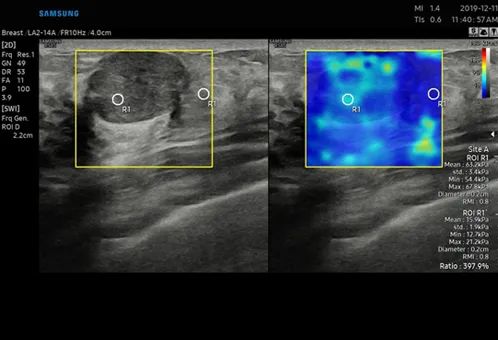

RS85 Prestige搭載了多款智慧應用,幫助臨床醫護人員做出更可靠的評估。如能夠提供HRI比率的EzHRI系統;S-Detect for Breast系統則能夠為乳腺超聲檢查提供標準化報告,並最佳化工作流;利用定量組織衰減測量來評估脂肪變性肝臟變化的TAI系統等。